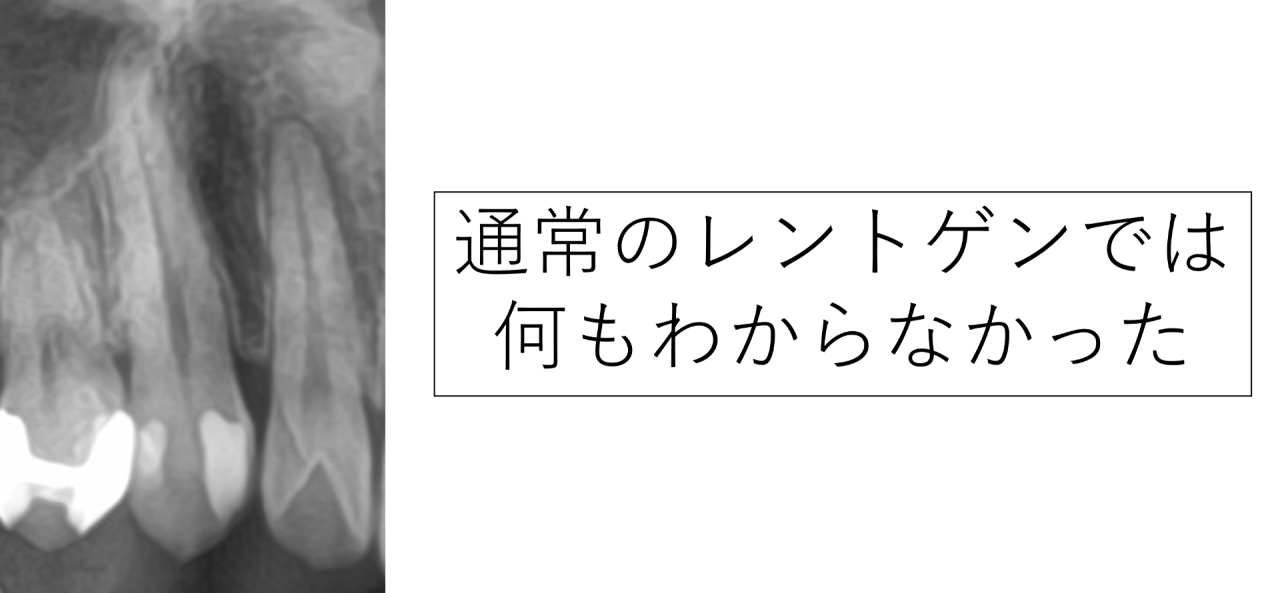

レントゲンを撮影した所、通常のレントゲンには何も写っておらず、原因が分かりませんでした。歯がひび割れした直後はレントゲンに写らないことがあるため、割れているだろうと前医は判断したのかもしれません。